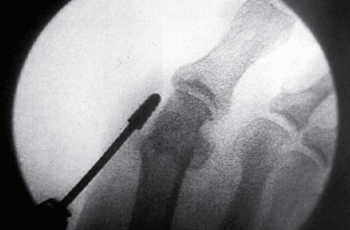

TÉCNICA QUIRURGICA

Haga click para agrandar las imágenes